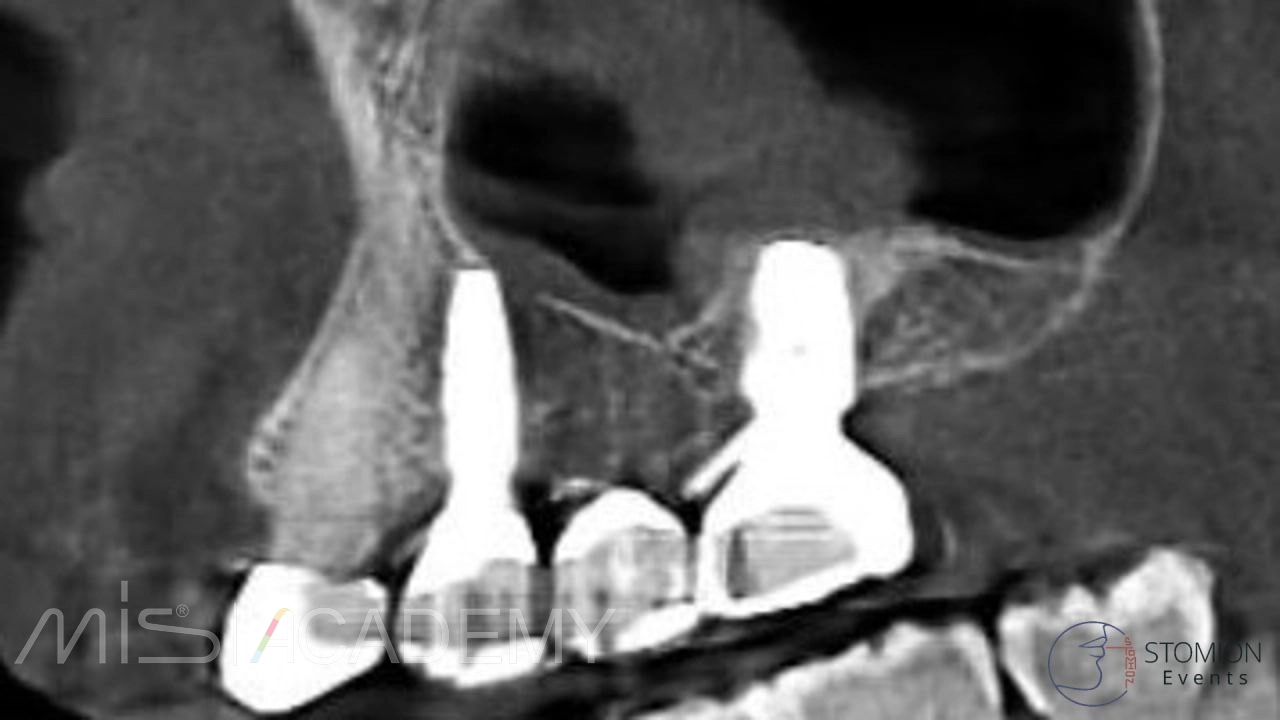

Одномоментная имплантация 2.5, 3.6, 4.6.